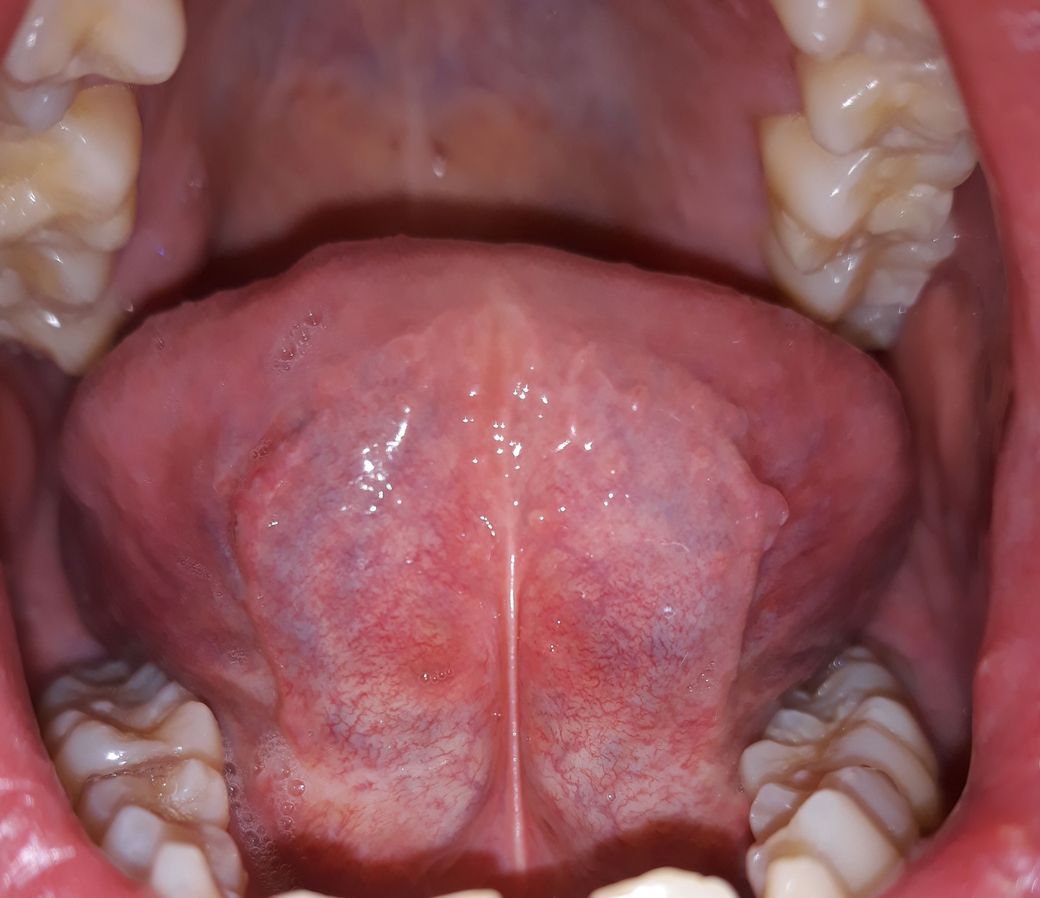

혓바닥 아래 상태가 정상인가요???

양치하다가 혓바닥 옆쪽 아래를 봤는데 잔핏줄도 많이 보이고 중간에 색깔도 군데군데 누런거같기도한데 만져보니깐 부드럽고 통증이나 불편한건 없습니다. 괜찮은건가요?

• 3번 째 사진

입 구석구석을 살펴보셨네요. 사진 올려주신 것만 봐서는 특별한 이상은 없어 보입니다. 증상도 없으니 괜찮다고 보셔도 되구요.

특별히 현재 통증 및 이물감 등이 있는 것이 아니라면 이상소견으로 보지는 않습니다.

만약 증상발생시는 치과에 내원해 보시는 것을 추천드립니다.